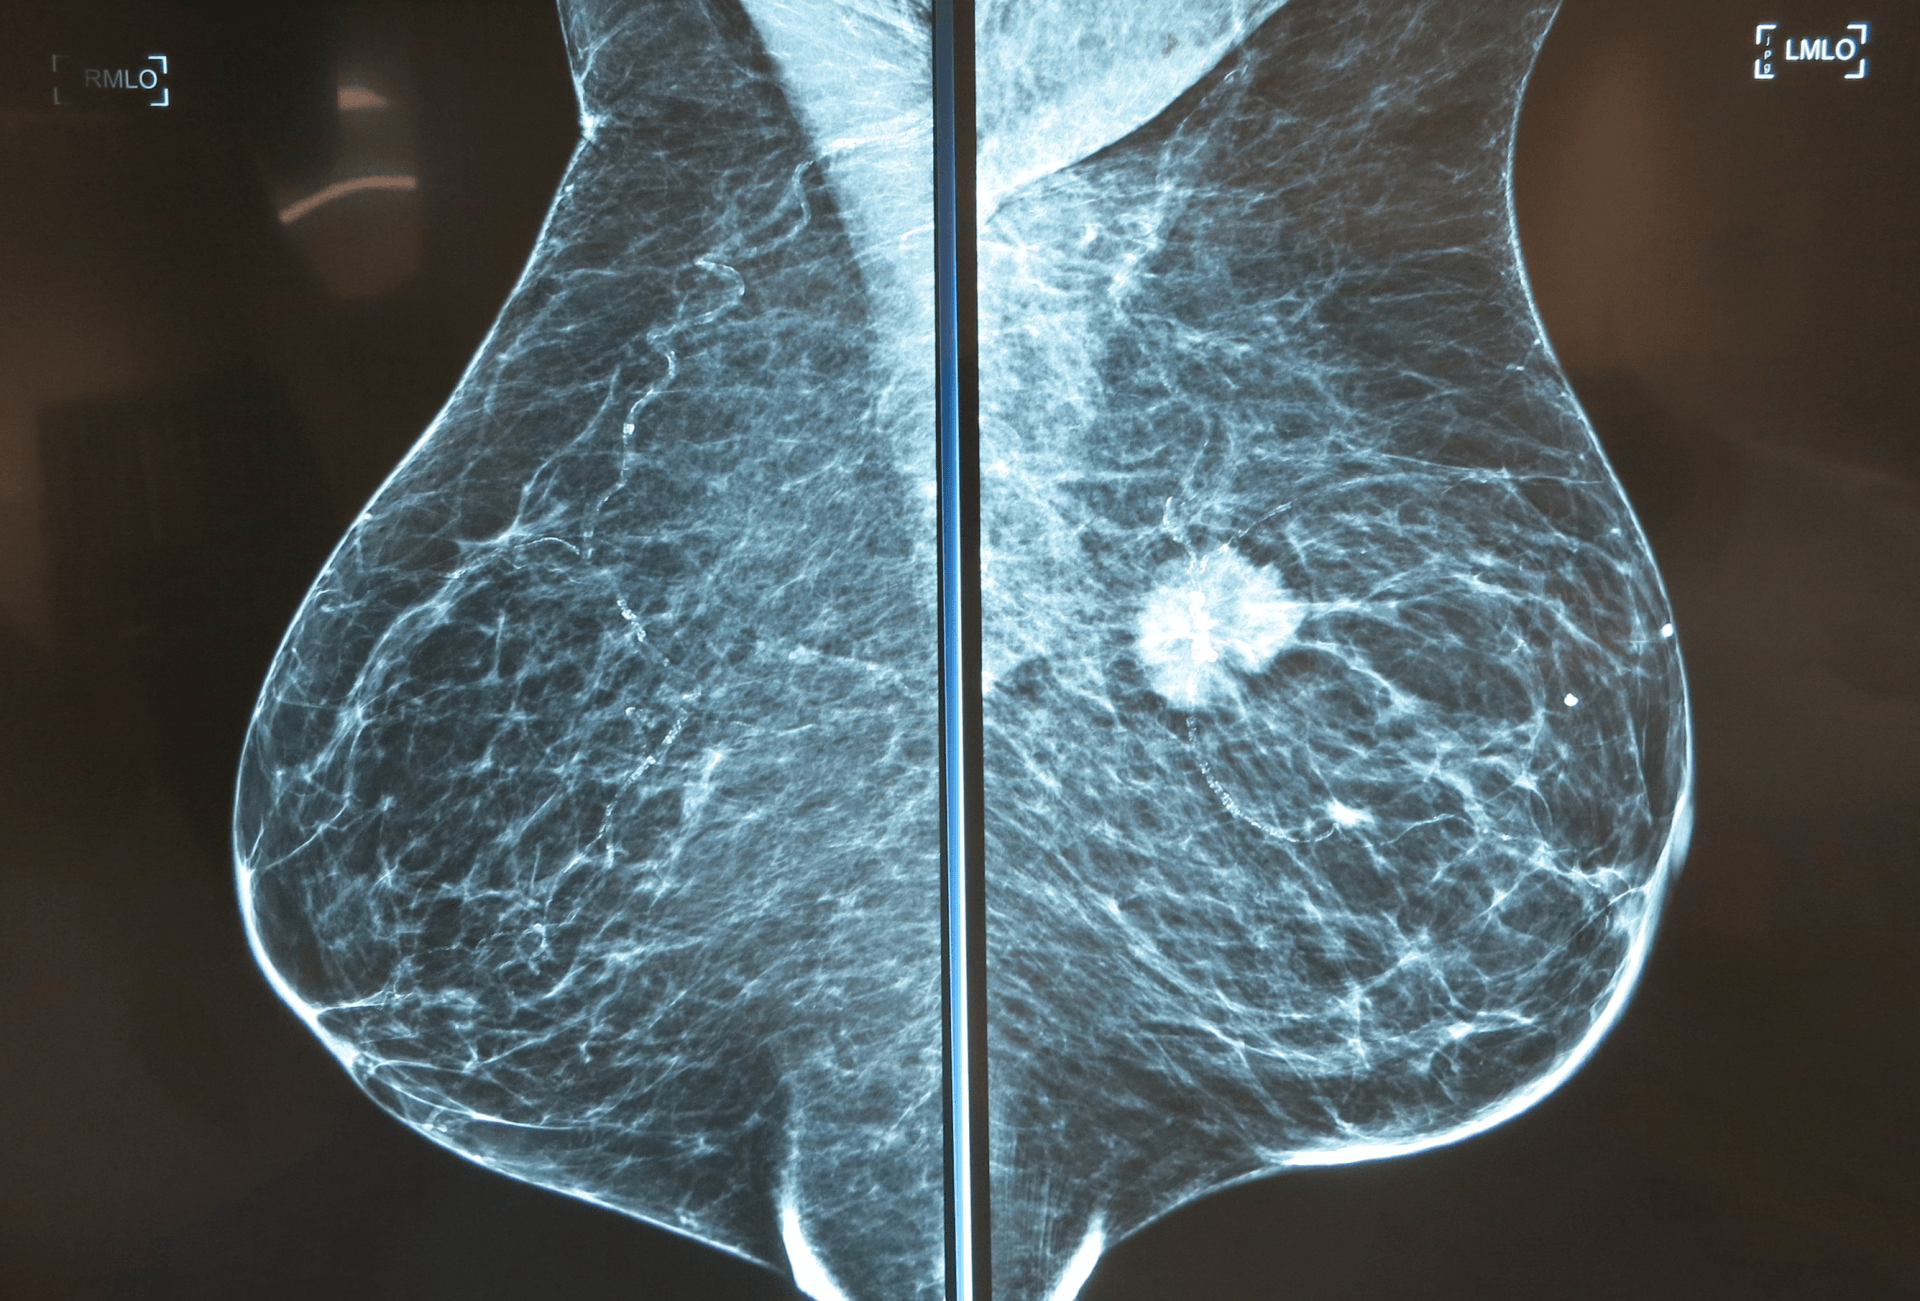

Breast cancer

A diagnosis of breast cancer can be frightening and confusing. There can be a lot of information to take in and it it feels as though you suddenly have to make all sorts of decisions without knowing what is the best thing to do.